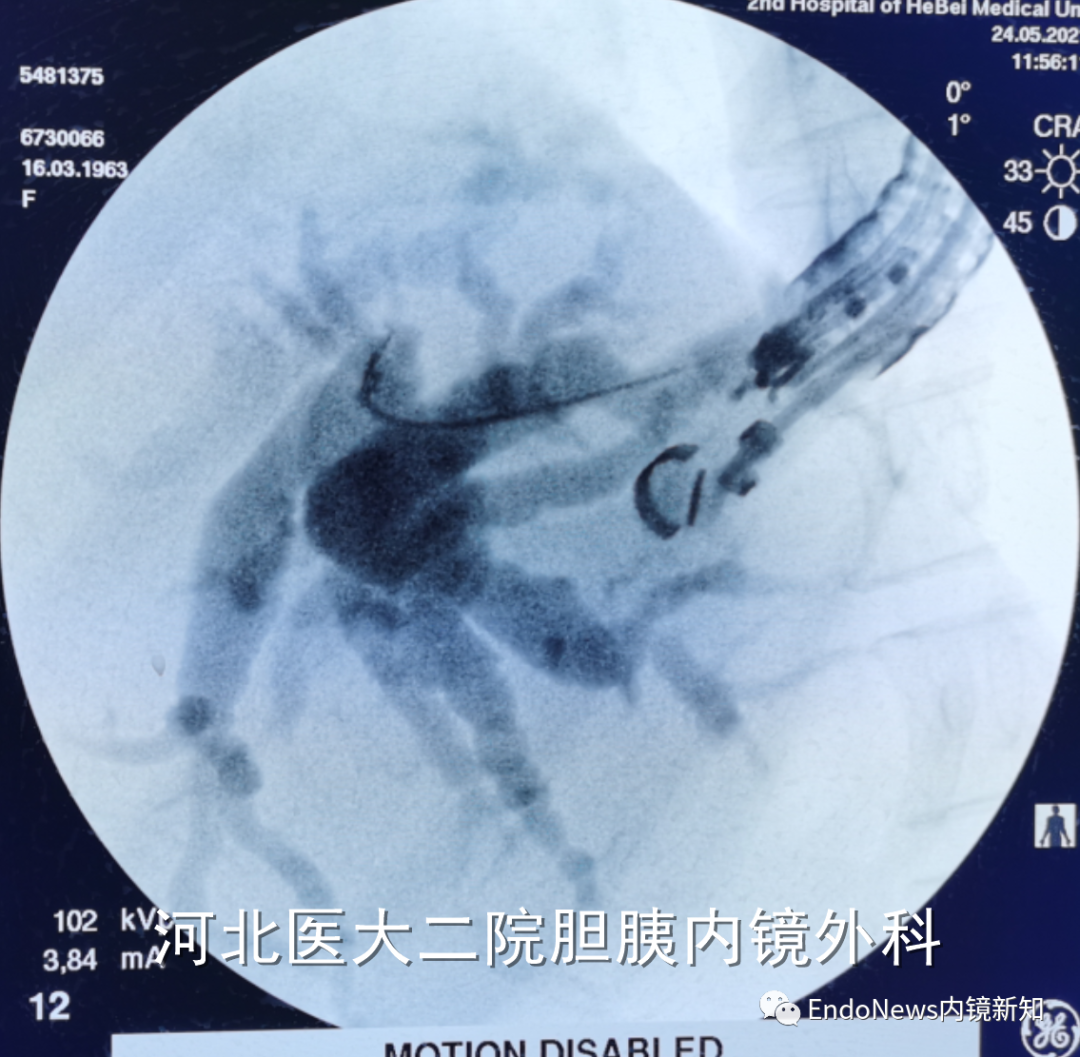

病例2:胆肠吻合口狭窄并右侧肝内胆管结石。

HGS造瘘,再碎石取石,置入双猪尾支架

在这个病例中,倘若是左肝管穿刺的第二段或第三段有结石,操作则更为困难,因此不同的病例还需要具体情况具体分析。

在下面肝内胆管结石的病例所示,这是一个进肝右叶管之后顺行放置双猪尾支架,在二期手术时将窦道扩开,用字母镜液电碎石,再在右侧肝内胆管管进行取石的病例。